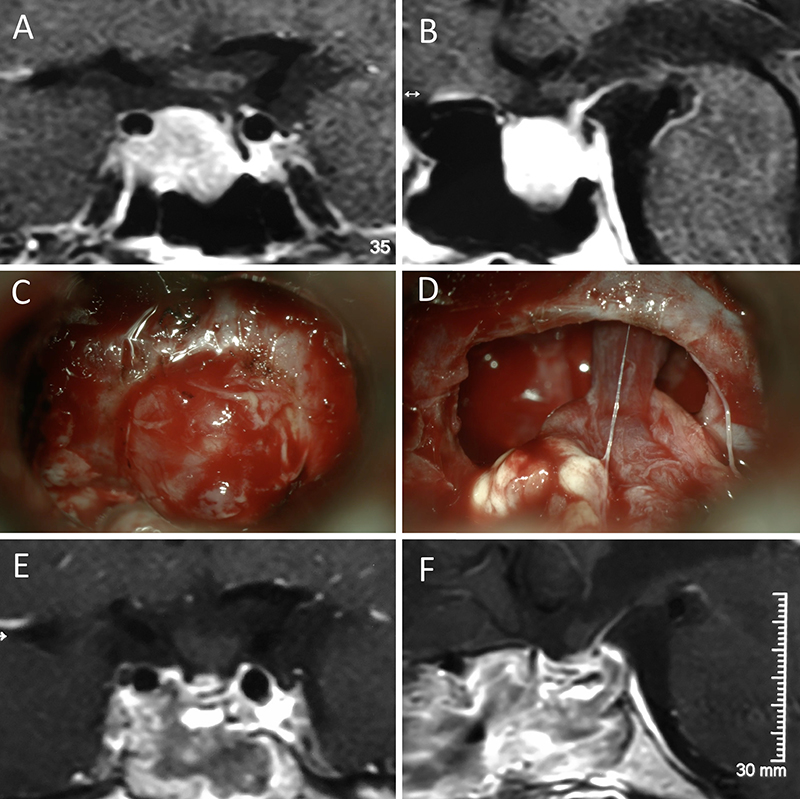

Figura 3: Macroadenoma no funcionante en un hombre de 64 años. El paciente presentó en el preoperatorio déficit visual que mejoró tras la cirugía. A-B: RM preoperatoria; C-D: intraoperatorio; E-F: RM postoperatoria.